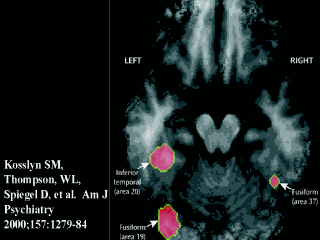

Let me walk you through this. About 10 percent of people are highly hypnotizable. They took eight such individuals and showed them identical patterns in color or in grayscale while they were undergoing positron emission tomography of the brain -- PET scanning -- which looks at functional changes in the brain, in this case, local changes in blood flow.